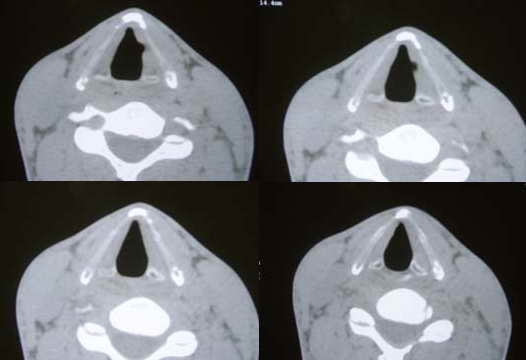

以下是引用wawaquan在2006-2-9 21:14:00的发言:[br]喉气囊肿又称喉膨出、喉憩室、猿猴气囊或喉气性疝,是喉室小囊的异常扩张,内含气体,可发生于一例或两侧,有先天性与后天性两种,分喉内、喉外、混合三型。可发生于任何年龄。[br] 诊断要点[br] 1.常有慢性咳嗽史或从事需强力鼓气、屏气职业史。[br] 2.喉内型常见症状为声音改变、嘶哑、咳嗽、喉鸣,甚至呼吸困难。喉外型则于颈部出现一圆形、柔软、可大可小肿物,皮肤色泽正常,无触痛,压之可变小,同时用听诊器可于颈部听到泄气声,屏气、吞咽时可出现或增大。有感染时局部均可疼痛。[br] 3.颈部凸起,触之甚软,穿刺可有气体。喉部可见囊性肿物自喉室突出,囊性肿物多不能推人喉室,针刺后可变小。屏气时拍颈部x线片或行ct检查可见局部圆形透亮区。